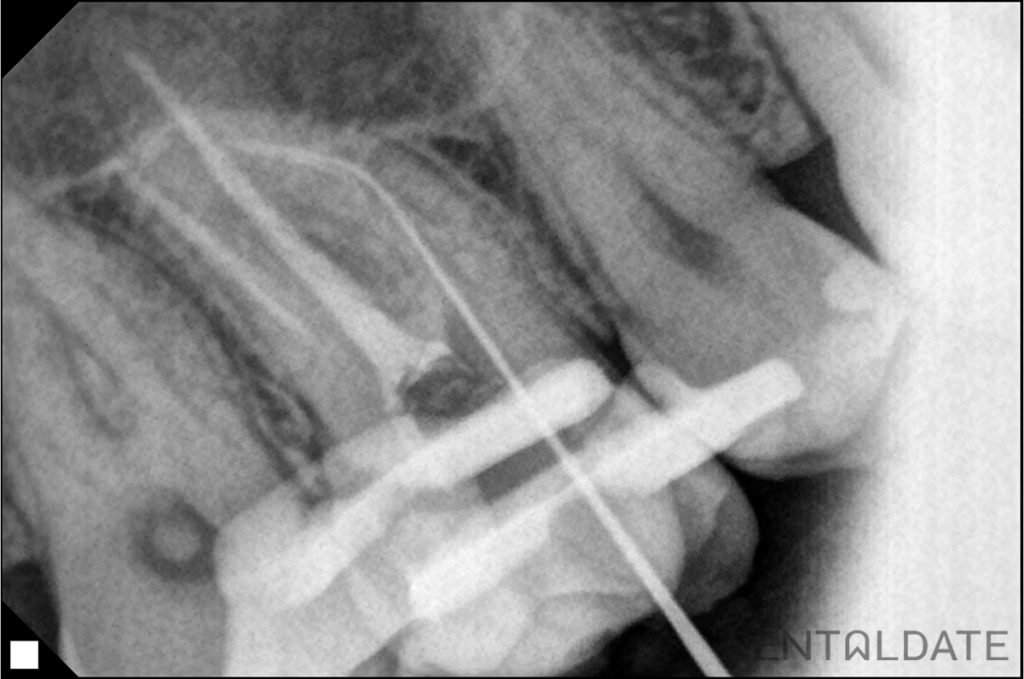

After 2 weeks the canals were mechanically and medically prepared for obturation and filled by the method of hot condensation of gutta-percha and siler AH plus. Filling.

Treatment was performed under dental microscope.